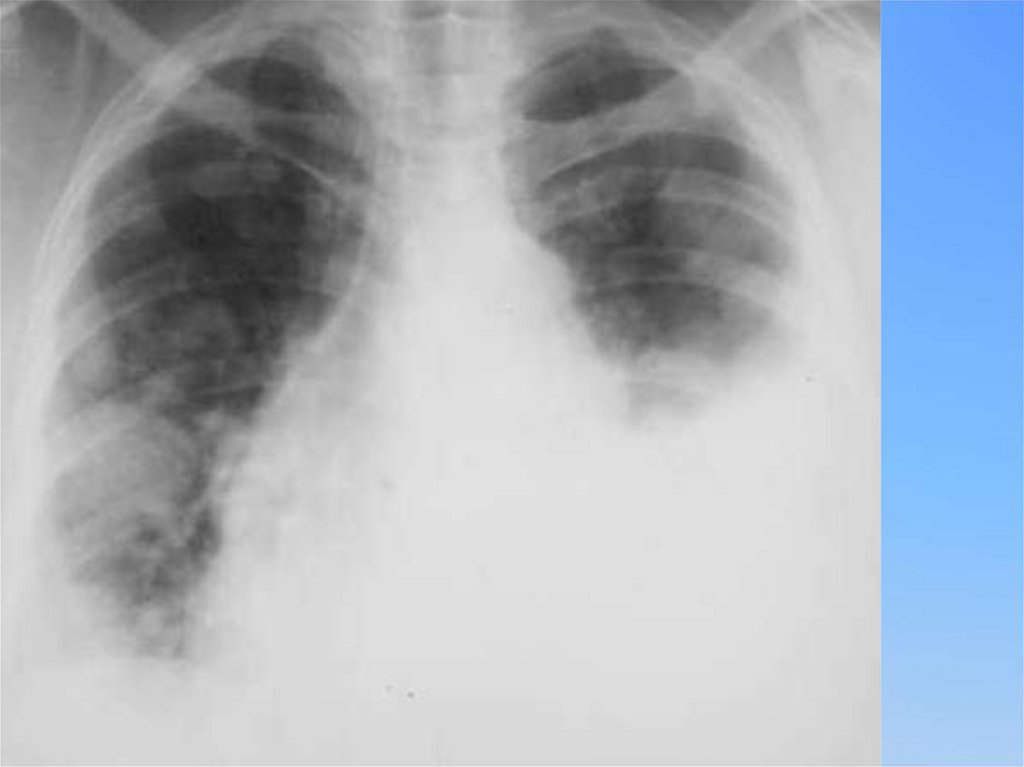

Рентгенологические

признаки

Туберкулез

Пневмония

Локализация

Верхние-задние

сегменты долей (С

1,2,6)

Базальные

сегменты (С

7,8,9,10)

Гомогенность

Не гомогенный

Гомогенный

Деструкция

50 и < %, часто

множественная, без

уровня

Редко - при ослож.

варианте, уровень

жидкости

Рентгенологически Инфильтрат в С 1,2,6

Инфильтрат в

базальных

сегментах

Ответная динамика Медленная, только на

болезни на

противотуберкулезные

антибиотики

препараты

Положительная

клиническая (2448 ч) , рентгенолог.

2 нед